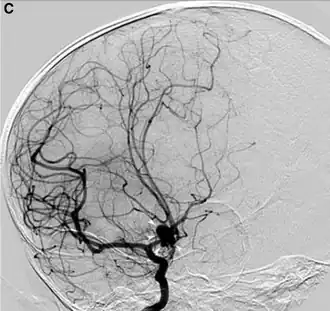

O exame padrão ouro para detecção de aneurisma cerebral não é a tomografia ou a ressonância magnética, e sim o cateterismo cerebral de 4 vasos (angiografia digital).